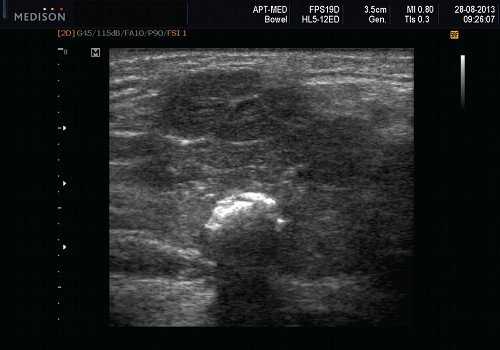

Данные УЗИ слюнных желез при карциноме

- Увеличенное солидное образование околоушной при ультразвуковом сканировании (примерно 75%) или поднижнечелюстной железы (примерно 25%)

- Особенности визуализации неспецифические

- Нечеткие или четко определенные границы.

- Гипоэхогенная, гомогенная или гетерогенная эхоструктура на УЗИ

- Отмечается внутренняя васкуляризация на цветном доплеровском исследовании.

- Могут наблюдаться аномальные интрапаротидные, перипаротидные, шейные лимфатические узлы.

Общие характеристики при ультразвуковом сканировании

- Лучший диагностический признак на УЗИ слюнной железы - Увеличенное солидное образование околоушной или поднижнечелюстной железы

Результаты ультразвукового исследования слюнной железы

- Серошкальное УЗИ. Одиночное солидное образование в паренхиме околоушной или подчелюстной железы. Может иметь хорошо выраженные, дольчатые или плохо очерченные / инфильтративные границы. Гипоэхогенная структура по отношению к паренхиме слюнной железы. Общее улучшение ультразвукового изображения задних структур. Иногда центральный кистозный компонент представляет некроз. Могут наблюдаться связанные аномальные интрапаротидные, перипаротидные, шейные лимфатические узлы

- Цветной допплер. Внутриузловая васкуляризация от умеренной до выраженной